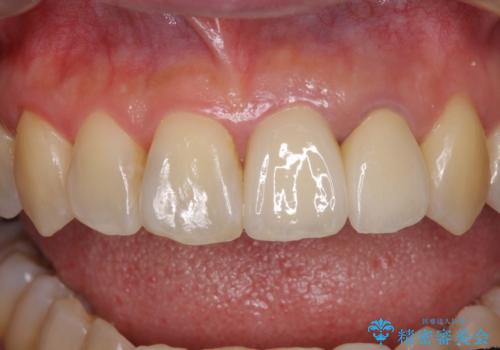

また、上顎前歯と下顎大臼歯に神経を取り除いた歯があったため、矯正治療後に、セラミッククラウンにて補綴することとしました。

矯正治療中に上顎前歯が下顎前歯を乗り越える際は、前歯でしか咬めない状況が続くため、食事など不便を感じましたが、治療後には前歯の痛みもなくなり、安定した咬み合わせとなりました。